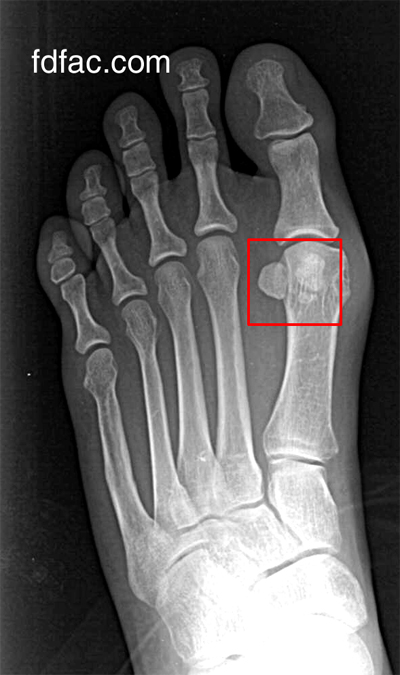

Beloved patient and avid hiker, WR, came in today after completing a rigorous 80 mile, 6-Day hike in Morocco. Prior to the hike, he purchased new hiking boots, which coincided with his onset of pain and formation of a never-before-seen lump at the front of his ankle. Fortunately, ultrasound and MRI showed nothing seriously wrong in this area other than focal swelling and inflammation consistent with tendonitis.

After evaluating his new hiking boots however, it was apparent that the top hook-lacing combination was crossing at exactly the same point where his pain and swelling was. In short, due to where the laces were crossing, the boot was strangulating the tendon beneath this point.

The easiest solution was to skip the uppermost eyelet on his boot, which was causing the irritation as the following image shows.